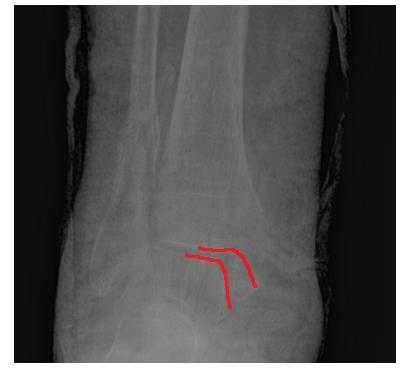

Переломы лодыжек следует дифференцировать с повреждением связок голеностопного сустава. При переломах боль, как правило, локализуется выше, максимальная болезненность определяется при пальпации костей, а не мягкотканных образований. Для постановки окончательного диагноза назначается рентгенография голеностопного сустава в двух стандартных проекциях (боковой и переднезадней). На снимках определяются линии изломов, направление и степень смещения отломков, вид подвывиха и степень расхождения берцовых костей. В сомнительных случаях назначают КТ голеностопного сустава, при необходимости оценить состояние мягкотканных структур - МРТ голеностопного сустава.

Пациентка Т. 80 лет. Травма за 3 недели до обращения, получила перелом обеих лодыжек правой голени со смещением, подвывихом стопы кнаружи. Обратилась в РТП, выполнена рентгенография, наложена гипсовая повязка. В связи с сохраняющимся выраженным отёком и болевым синдромом обратилась в клинику К+31.

На рентгенограммах в гипсе определяется значительный подвывих таранной кости кнаружи, консолидирующийся перелом нижней трети малоберцовой кости.